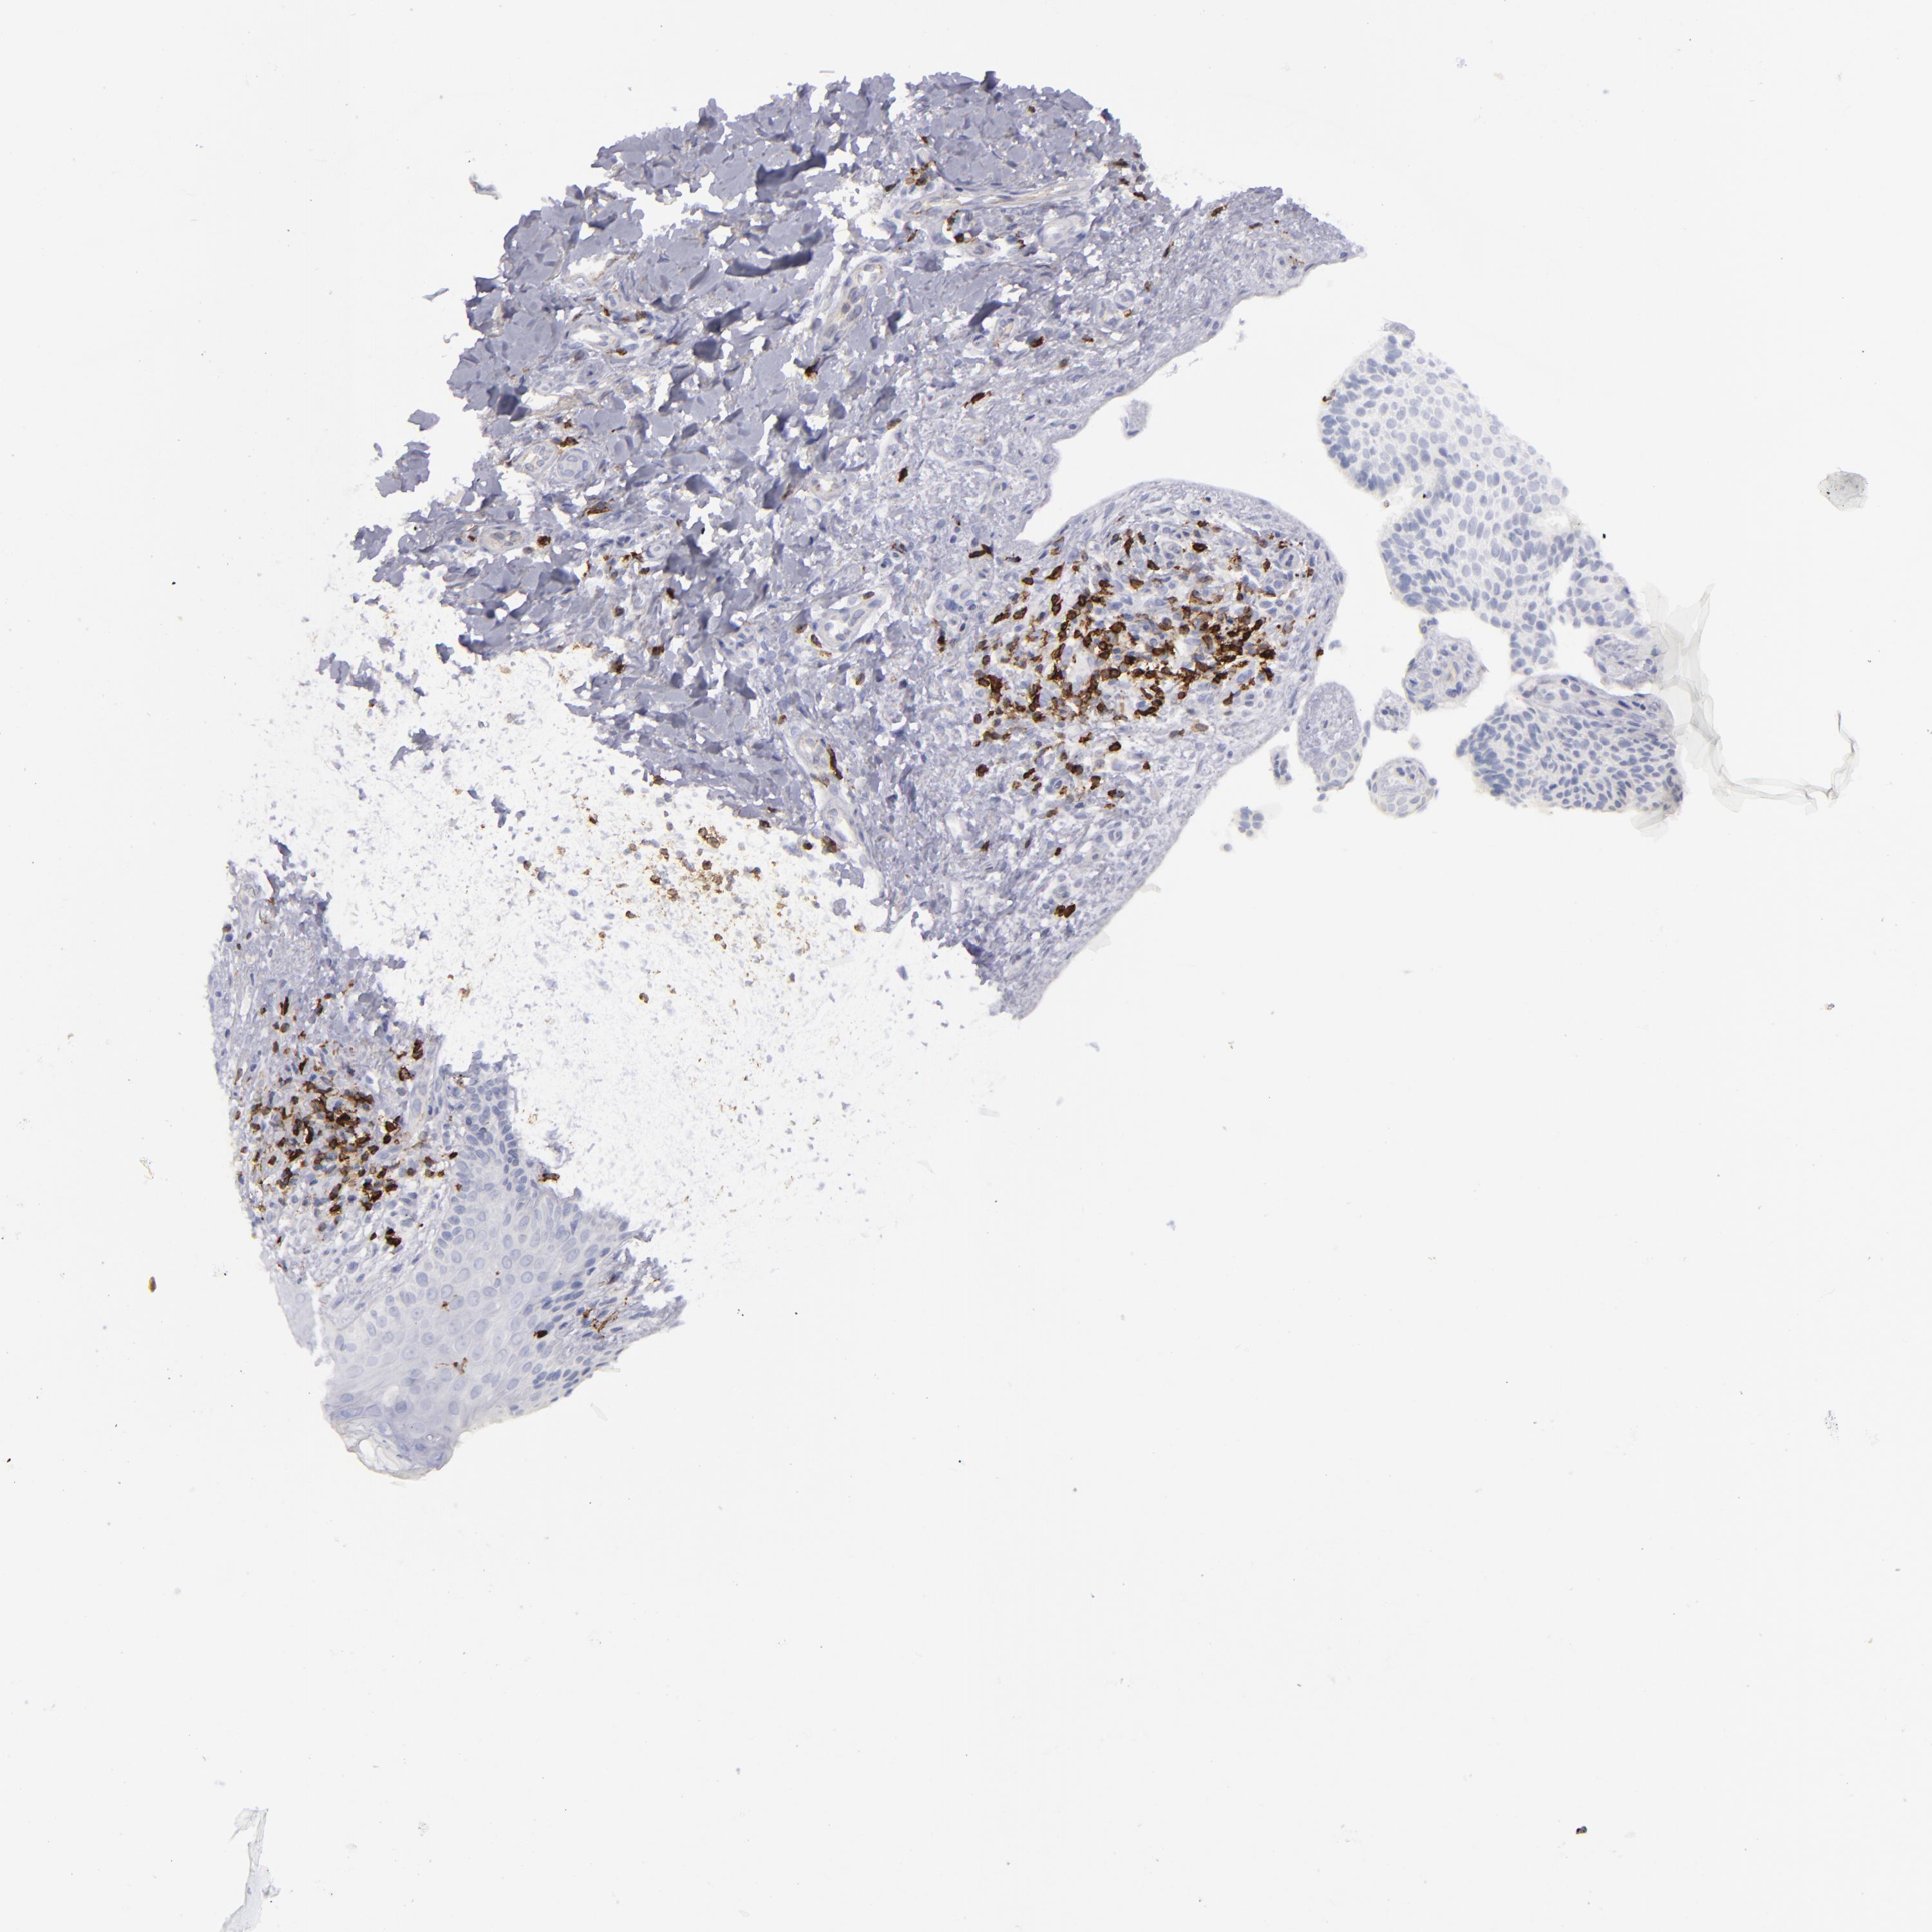

SKIN CANCER - Protein expressioni

A mouse-over function shows sample information and annotation data. Click on an image to view it in a full screen mode. Samples can be filtered based on level of antibody staining by selecting one or several of the following categories: high, medium, low and not detected. The assay and annotation is described here.

Each image is clickable and will lead to virtual microscopy that enables deeper exploration of all samples and also displays staining intensity scores, fraction scores and subcellular localization as well as patient and tissue information for each sample.

Antibody CAB002420

Basal cell carcinoma

BCC, high aggressive